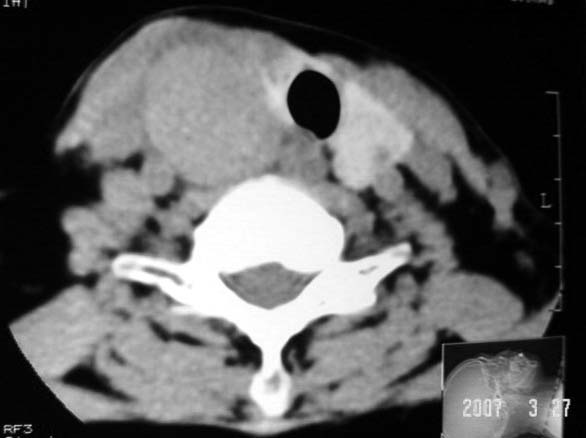

标题: CT7324:女57岁,右颈部肿物2年.

右侧甲状腺区均匀密度软组织肿块,无坏死及钙化,边缘光整,与周围组织分界清晰,病史较长,首先考虑右侧甲状腺腺瘤。